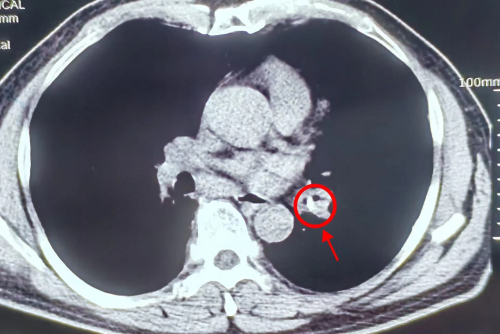

(影像检查发现患者的左下支气管有一块阴影)

刘建勋家住娄底双峰县,三年前检查出患有慢性支气管炎病史,每次有症状时用点消炎止咳药就会有所缓解。但在最近半个月,刘建勋服用药物后咳嗽、气促症状并无好转,而且出现反复发热、胸痛症状。3月9日,他在家人的陪同下来到91短视频 (南华大学附属长沙中心医院)呼吸与危重症医学科就诊。呼吸与危重症医学科副主任、副主任医师刘达仔细询问病史,结合CT检查发现他的左下支气管有一块阴影,痰病原学检测为口腔定植菌,考虑支气管异物可能性大,建议刘大爷做一个肺部纤维支气管镜的检查以明确诊断。